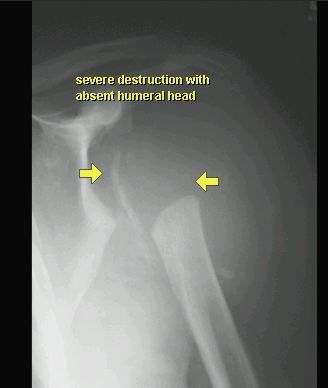

STAW CHARCOTA

RTG